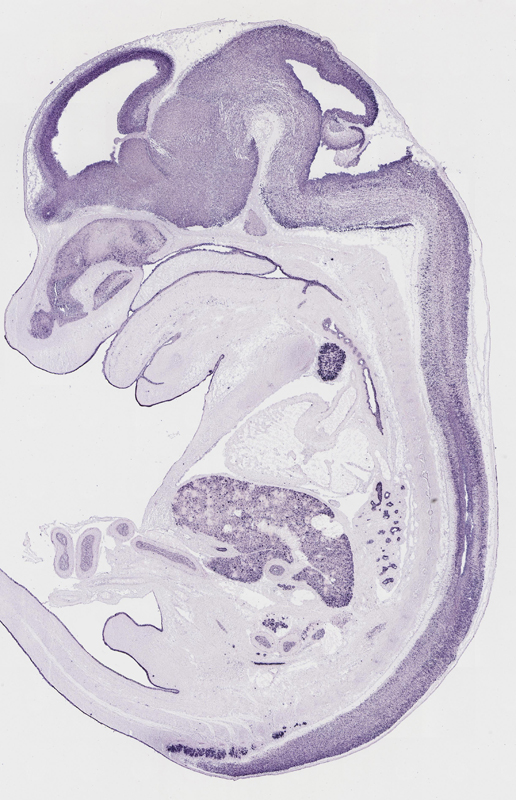

Specimen

euxassay_003287_02:

embryonic day 14.5